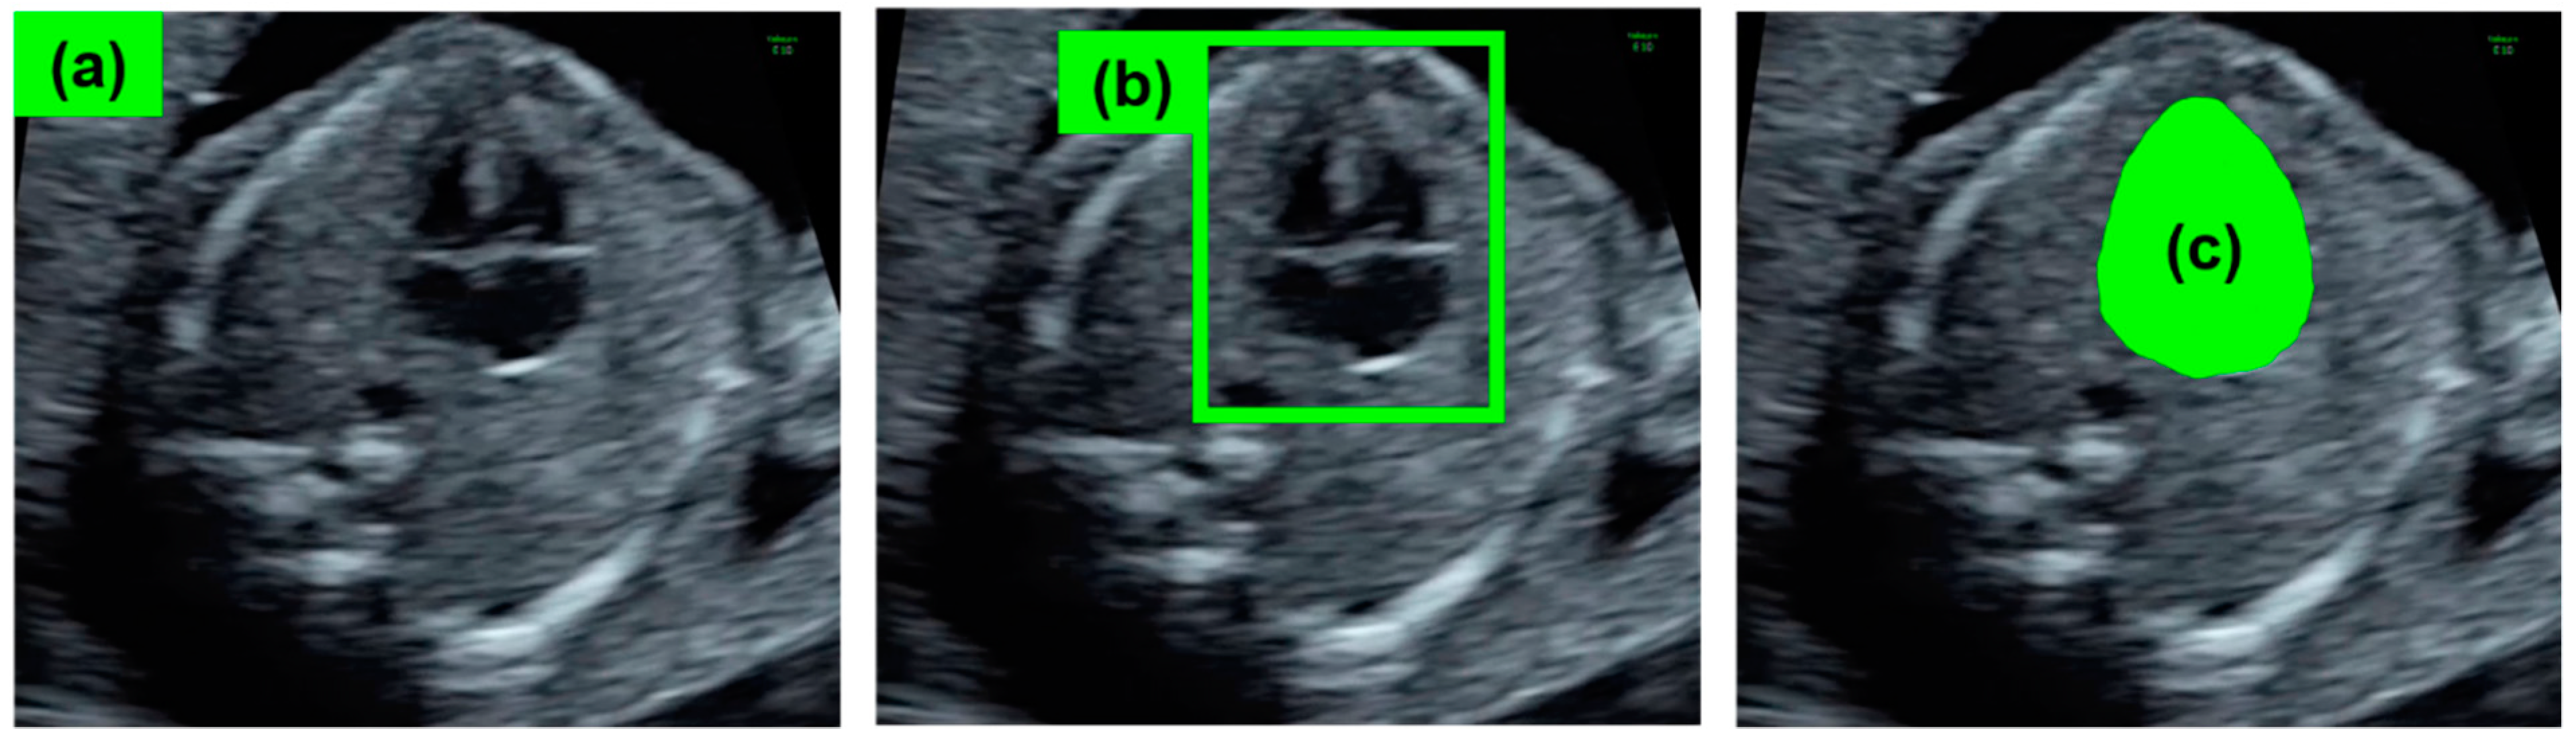

- Yasutomi, S.; Arakaki, T.; Matsuoka, R.; Sakai, A.; Komatsu, R.; Shozu, K.; Dozen, A.; Machino, H.; Asada, K.; Kaneko, S.; et al. Shadow Estimation for Ultrasound Images Using Auto-Encoding Structures and Synthetic Shadows. Appl. Sci. 2021, 11, 1127. [Google Scholar] [CrossRef]

- Komatsu, M.; Sakai, A.; Komatsu, R.; Matsuoka, R.; Yasutomi, S.; Shozu, K.; Dozen, A.; Machino, H.; Hidaka, H.; Arakaki, T.; et al. Detection of Cardiac Structural Abnormalities in Fetal Ultrasound Videos Using Deep Learning. Appl. Sci. 2021, 11, 371. [Google Scholar] [CrossRef]